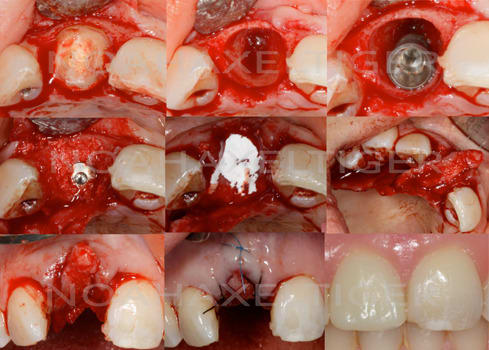

Le cas EII sur 12

positionnement de l'implant en ménageant un espace en vestibulaire qui st comblé avec de l'os synthétique car l'espace est important et il y a une perforation de la corticale vestibulaire en regard de l'apex de la dent.

pour recouvrir tout cela et gagner un peu de volume vestibulaire

un lambeau palatin pédiculé qui après une rotation va recouvrir l'implant et la greffe.

Voila un exemple de conjonctif pédiculé palatin.

Les gros avantages par rapport à ta technique sinclair sont :

1- mobilisation d'un plus gros volume de tissus pour gonfler en vestibulaire.

2- cicatrisation de première intention au niveau du palais puisque l'ensemble du site prélevé est couvert par ta fenêtre d'accès

3- peu de suite post opératoire.

parfois ça rend bien service...

suite à une splendide ratage incontrôlé ( méa culpa, méa culpa...)

1-après pose de l'implant; nécrose du lambeau, beurkk..

2-nouveau lambeau

3-prélèvement d'un énorme steak pédiculé (faut pas avoir peur d'aller loin!)

4-sutures à donf

pour la petite histoire j'ai fait ça en urgence un 23 décembre: tu parles d'un cadeau!

5-cicatrisation, c'est mieux mais c'est pas encore ça, donc rebelote!

6-prélèvement d'un p'tit bout du palais

7- un peu de collagène sur la plaie palatine

8-greffon

9 sutures

10-11- cicatrisation

j'ai oublié de faire des photos la dernière fois que j'ai vu la patiente mais l'aspect de la gencive est nickel et l'implant est parfaitement ostéo-intégré.